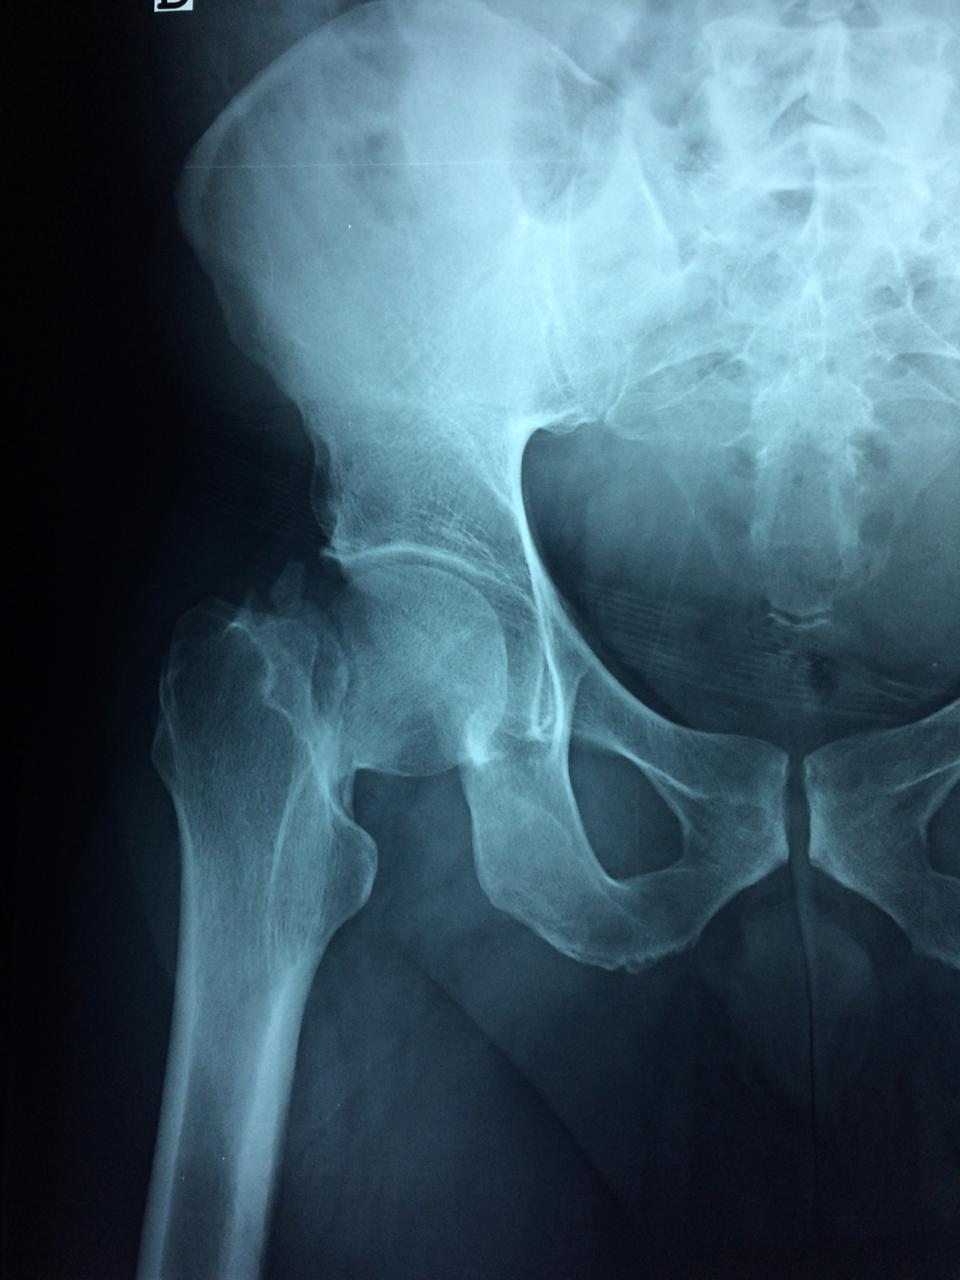

Cirugías de Cadera

La cirugía de fractura de cadera se realiza para reparar una ruptura en la parte superior del hueso del muslo. Este hueso se denomina fémur.

Es parte de la articulación coxofemoral. Si una fractura de cadera no recibe tratamiento, es posible que deba permanecer en una silla o en la cama.